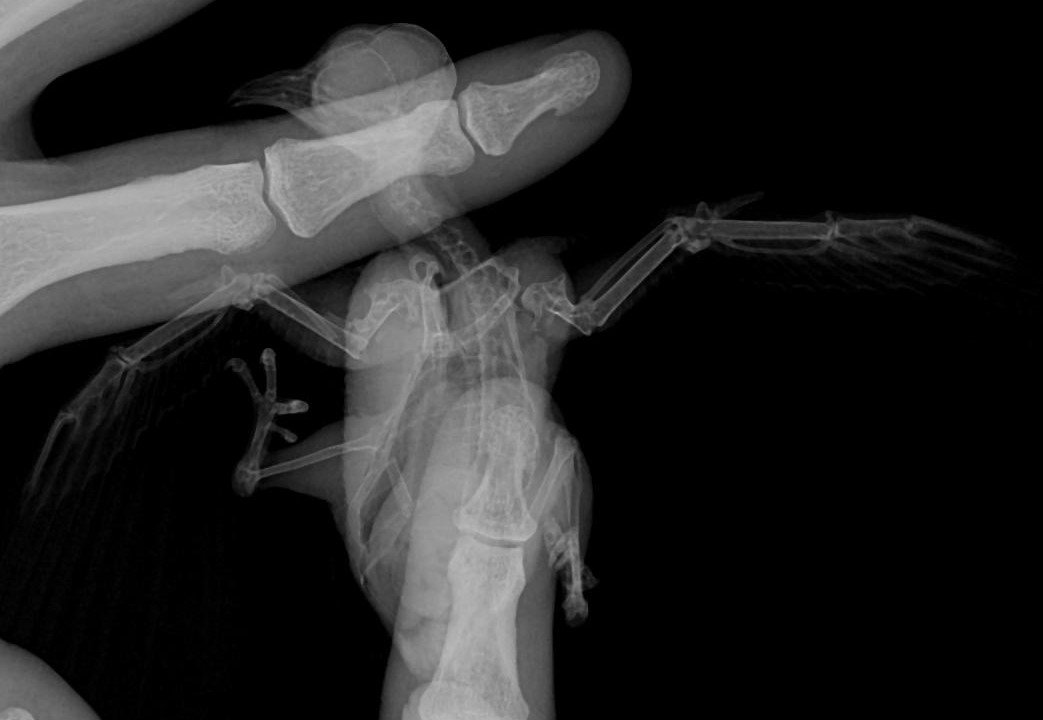

Добрый день. Три дня назад подобрал на улице птицу с неестественным положением правого крыла (о том, что это стриж узнал от ветеринарного врача). Занес в ближайшую ветеринарную клинику, где врач, осмотрев и ощупав птицу (рентгена в клинике не было), сказал, что перелома нет, скорее всего стриж ударился о провод и ему необходимо несколько дней для восстановления. Никогда не имел дел не только со стрижами, но и с птицами вообще, но решил попробовать его спасти. Живет в коробке примерно 30х30х30, кормлю опарышами, так как пока не нашел других насекомых, этот вопрос решу в ближайшее время. Вопрос с питанием отдельная проблема. Больше всего меня беспокоит его крыло. Сегодня свозил птичку на рентген. Врач хотя и увидел перелом, но о лечении птиц знает примерно столько же сколько и я. Даже не знал, как называется сломанная кость (называл её маленькой) Я потом посмотрел в интернете, что это лучевая кость. А локтевую кость называл маховой. Предложил зафиксировать крыло и, прижав крылья к телу, замотал его эластичным бинтом. Приехав домой, я снял эту повязку. Не знаю смогу ли найти ветеринара по птицам, а пока прошу совета и помощи у знающих людей. Есть ли шанс вылечить птицу с таким переломом? Нужно ли её пеленать, как сделал этот врач? Может быть поместить стрижа в маленькую коробочку, чтобы у него не было возможности махать сломанным крылом? В общем, что сейчас делать с птичкой? Спасибо за советы PS На последнем снимке стрижик завернут в эластичный бинт